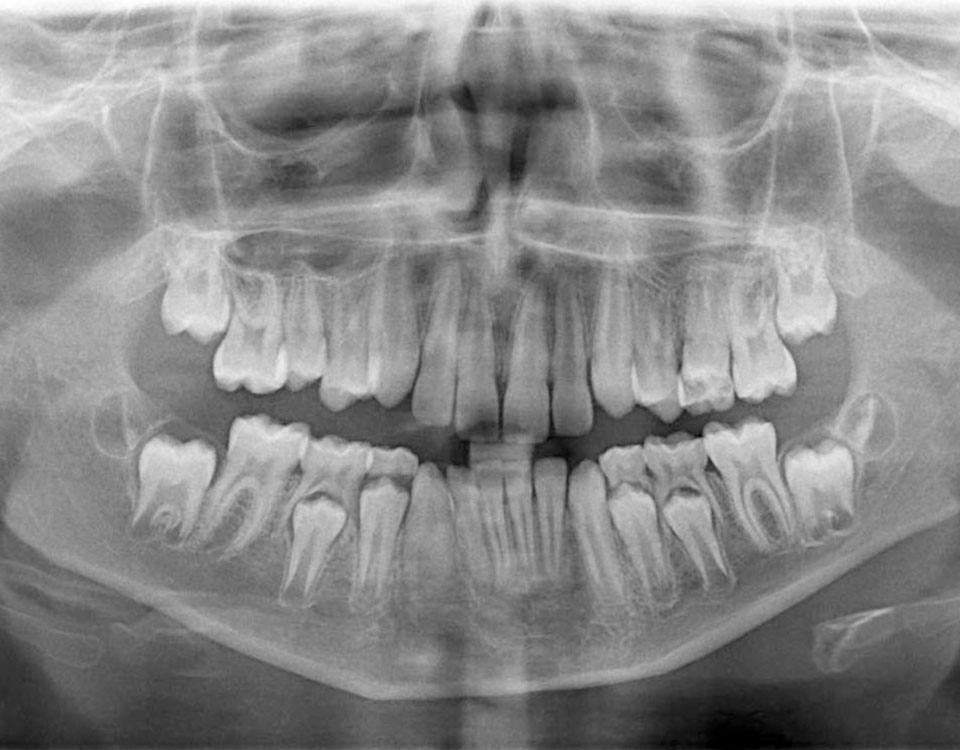

Ortopantomografia (Raio-X panorâmico)

A Ortopantomografia é uma técnica de radiografia panorâmica que utiliza raios X para fornecer informações detalhadas sobre as estruturas dentárias e a anatomia oral. Permite obter informações acerca dos dentes, das estruturas anexas como seios maxilares, maxila e mandíbula.